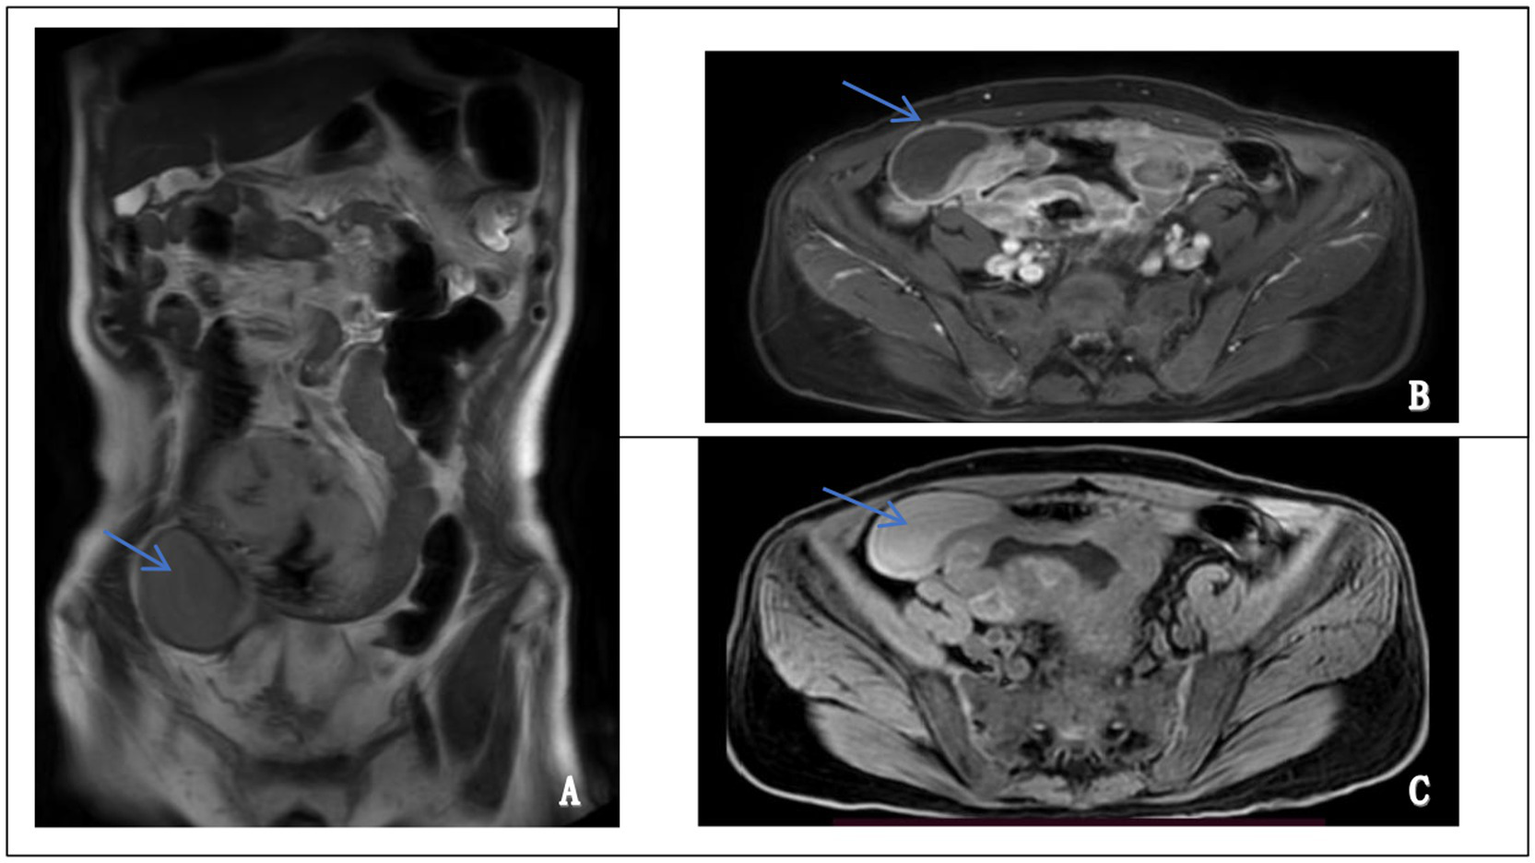

Abdominal contrast-enhanced MRI performed on October 17, 2024, revealed an irregular, ring-enhancing mass located in the right lower quadrant. The lesion exhibited hyperintensity on T2-weighted images and hypointensity on T1-weighted images, with heterogeneous enhancement after contrast administration. Although intestinal lymphoma was initially suspected based on imaging features, there were no definitive signs of continuity between the mass and the intestinal lumen. A pelvic stromal tumor with central necrosis could not be excluded (Figure 2). These findings, in conjunction with inconclusive endoscopic biopsies, prompted surgical exploration for definitive diagnosis and treatment.

Figure 2

Magnetic resonance imaging (MRI) features of the abdominal mass. (A) Coronal T2-weighted image showing a well-defined, hyperintense mass in the lower abdomen (left panel, arrow). (B) Axial contrast-enhanced image demonstrating heterogeneous enhancement of the lesion, suggestive of a solid, vascularized tumor (upper right panel, arrow). (C) Axial T1-weighted image revealing a hypointense mass at the corresponding site (lower right panel, arrow).